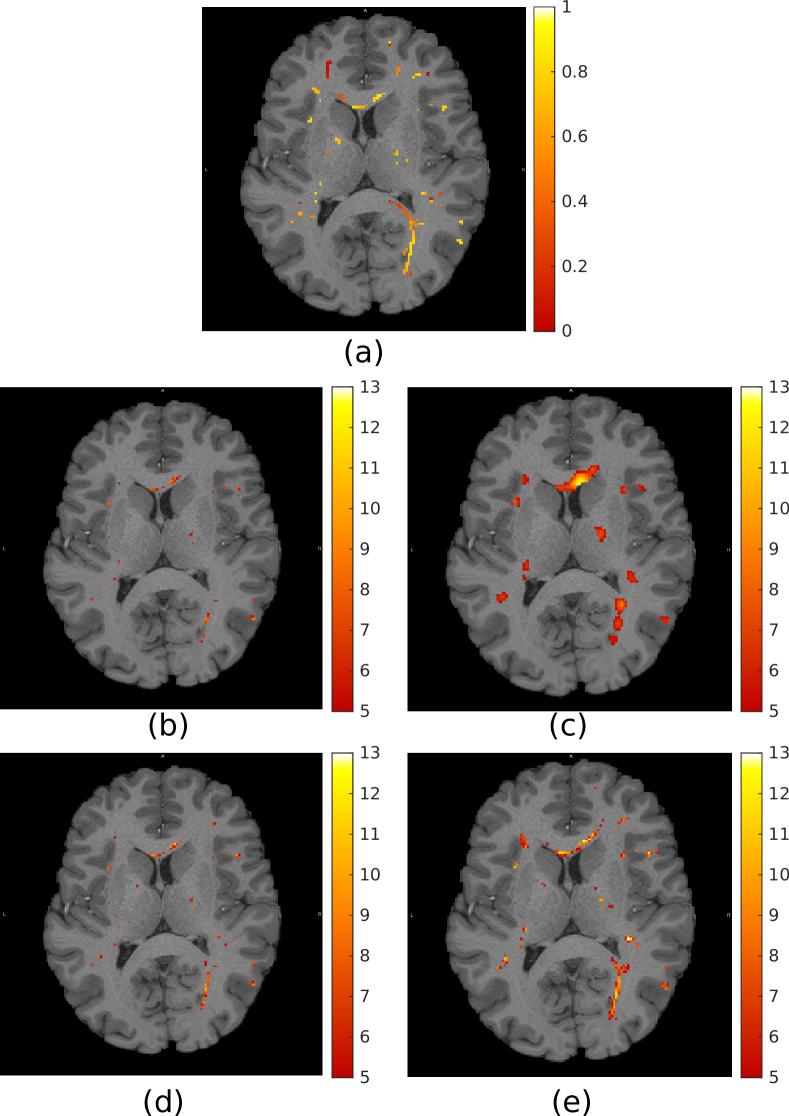

The 959595 semi-synthetic time-series phantoms were filtered using both isotropic Gaussian filtering and the proposed graph filtering approach. The resulting filtered volumes were subjected to a standard GLM-based activation mapping using the SPM toolbox. Figure 2 shows a comparison of the results obtained by using the various filtering methods. For small filter sizes, isotropic Gaussian filtering is capable of detecting the subtle shapes of the activations, but with reduced sensitivity compared to graph filtering. More activations are detected with larger filter sizes, but at the cost of diminished specificity. In contrast, the shapes of the activations detected through graph filtering are consistent across filter sizes.

Fig. 2: (a) Example synthetic activation pattern. Dot-shaped activations extend linearly in the plane orthogonal to the image. (b)-(e) t-maps obtained from analysis conducted using: (b)-(c) isotropic Gaussian filtering, FWHM=2FWHM2\text{FWHM}=2mm and 666mm respectively; (d)-(e) graph filtering, τ=1.3𝜏1.3\tau=1.3 and 3.33.33.3 respectively. All t-maps thresholded at t=5𝑡5t=5 and overlaid on the T1 image of the corresponding subject.